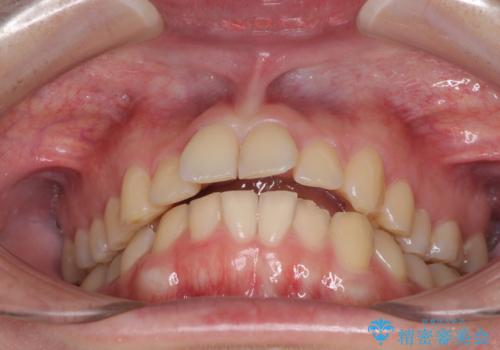

- 食いしばりが気になっていたとのことで来院された患者様です。

当初は睡眠時のマウスピースのみの製作をご希望でしたが、矯正治療の提案をしたところ、インビザラインにて矯正治療を行うこととなりました。

矯正治療中に食いしばりがより強くなることがあるため、半年に1回のペースでボツリヌストキシンによる咬合力緩和を並行して行うこととしました。

咬合力の緩和と食いしばりがちな咬み合わせが改善され、顎の負担が大幅に軽減されました。